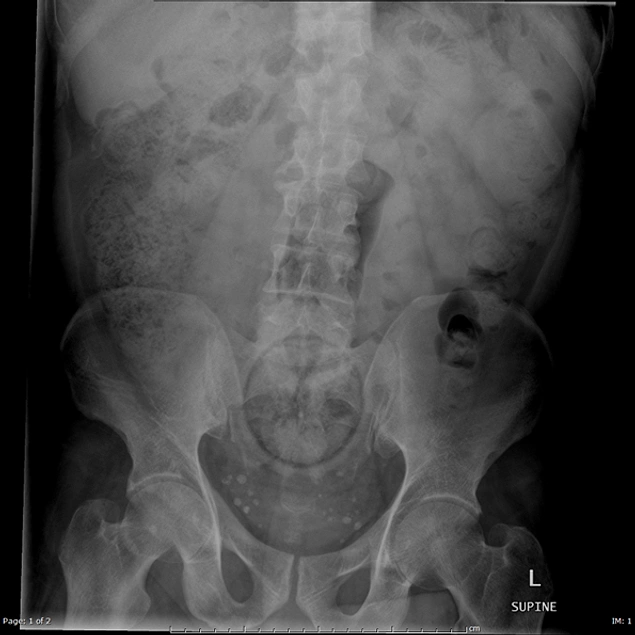

Необычные рентгеновские снимки: то, что скрыто внутри

Раздел: Визуальный дайджест